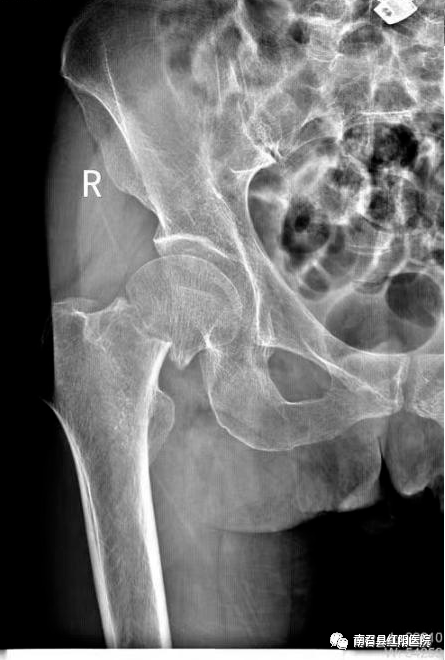

另一老年男性,孤寡老人,在养老院走楼梯时不慎摔倒,致股骨颈骨折,家中无人照顾,养老院请专门护工护理,与患者及其亲属商议后拟行手术治疗,手术顺利,术后恢复良好,术后3天即可拄拐下床活动,现患者已好转出院。